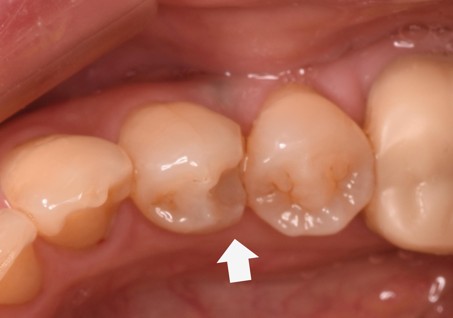

治療後 ![]() |

痛みが出たり、欠けたりすることもなく経過は良好です。 |

セラミックが多く配合されていることにより、経年劣化は従来の樹脂よりとても少ないですが、変色することがあります。 |